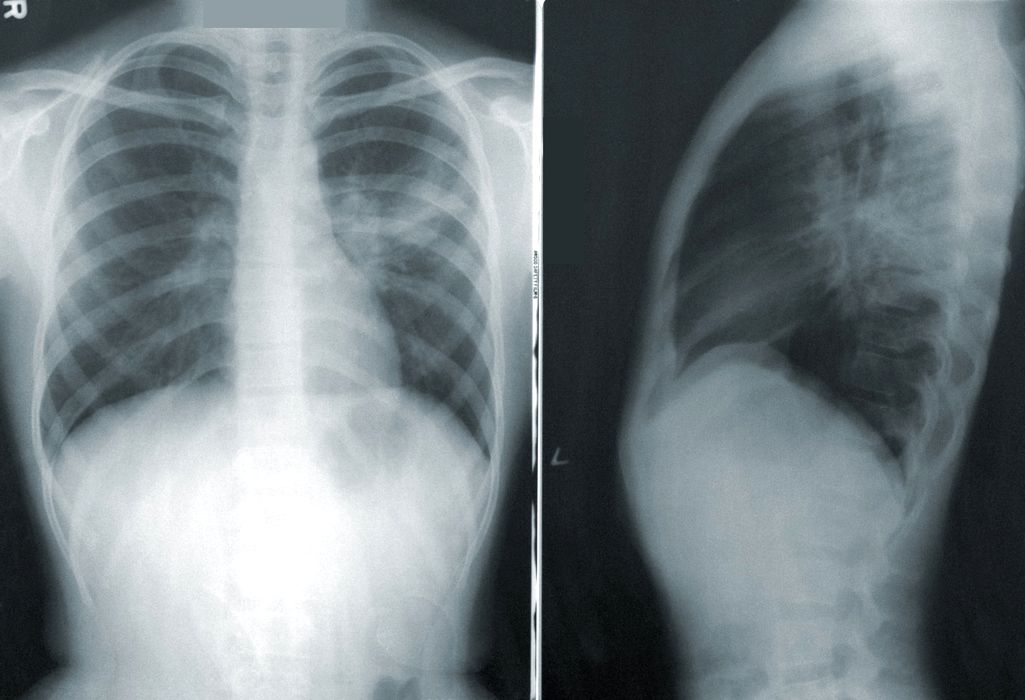

Șase forme ale bolii COVID-19 şi simptomele aferente, descoperite de cercetători britanici

O aplicaţie care monitorizează simptomele COVID-19, cunoscută în întreaga lume, a fost luată în vizor şi de cercetătorii britanici. Specialiştii şi oamenii de ştiinţă de la King’s College au extras datele din aplicaţie şi le-au […]